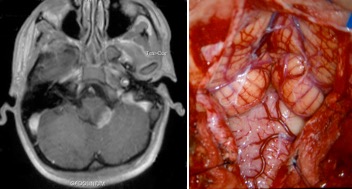

l’abord postéro-latéral de la moelle allongée

les lésions intra-axiales qui affleurent au plan pial peuvent être abordées par une craniotomie occipitale médiane, avec dépose de l’arc de C1 et en élargissant la craniotomie du côté de la lésion. la dissection de la tonsille donne accès à la citerne latéro-bulbaire et l’angle ponto-cérébelleux.

cette voie d’abord nécessite une dissection soigneuse des nerfs mixtes et de l’artère vertébrale. l’abord bulbaire correspond au sillon pré-olivaire.

la section de la première digitation du ligament dentelé (repère de l’artère vertébrale) permet de gagner un peu de place latéralement mais n’améliore pas sensiblement l’axe de vision, qui reste tangentiel à la moelle allongée.